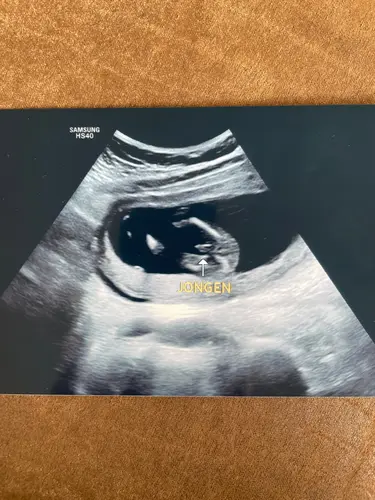

Dit is die van ons met 14+2 - soms twijfel ik nog wel een beetje omdat “het” best klein is!?

8 maanden geleden

Dit formaat was het bij ons 1e zoontje ook op de echo!😋

Ahhh kijk dat is goed om te horen!